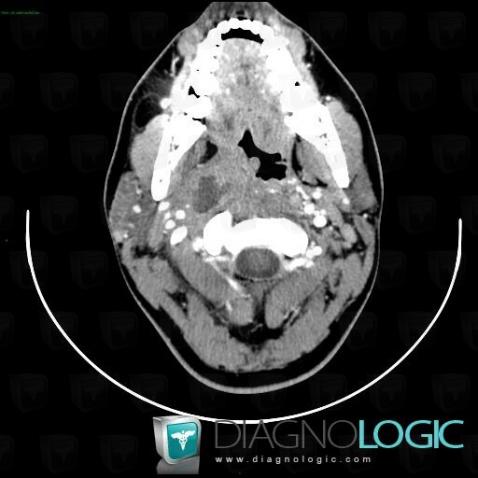

Abscess, Deep facial spaces, CT

Here is the specific information in the key image above:

- Diagnosis Abscess, Location(s) Deep facial spaces, with gamuts Retropharyngeal space lesion, Cystic cervical mass, Parapharyngeal space lesion, Prevertebral space lesion

Intraparotid lymph node, Parotid and other salivary glands, CT

- Diagnosis Intraparotid lymph node, Location(s) Parotid and other salivary glands, with gamuts Parotid gland lesion / enlargement, Multiples parotid gland lesions